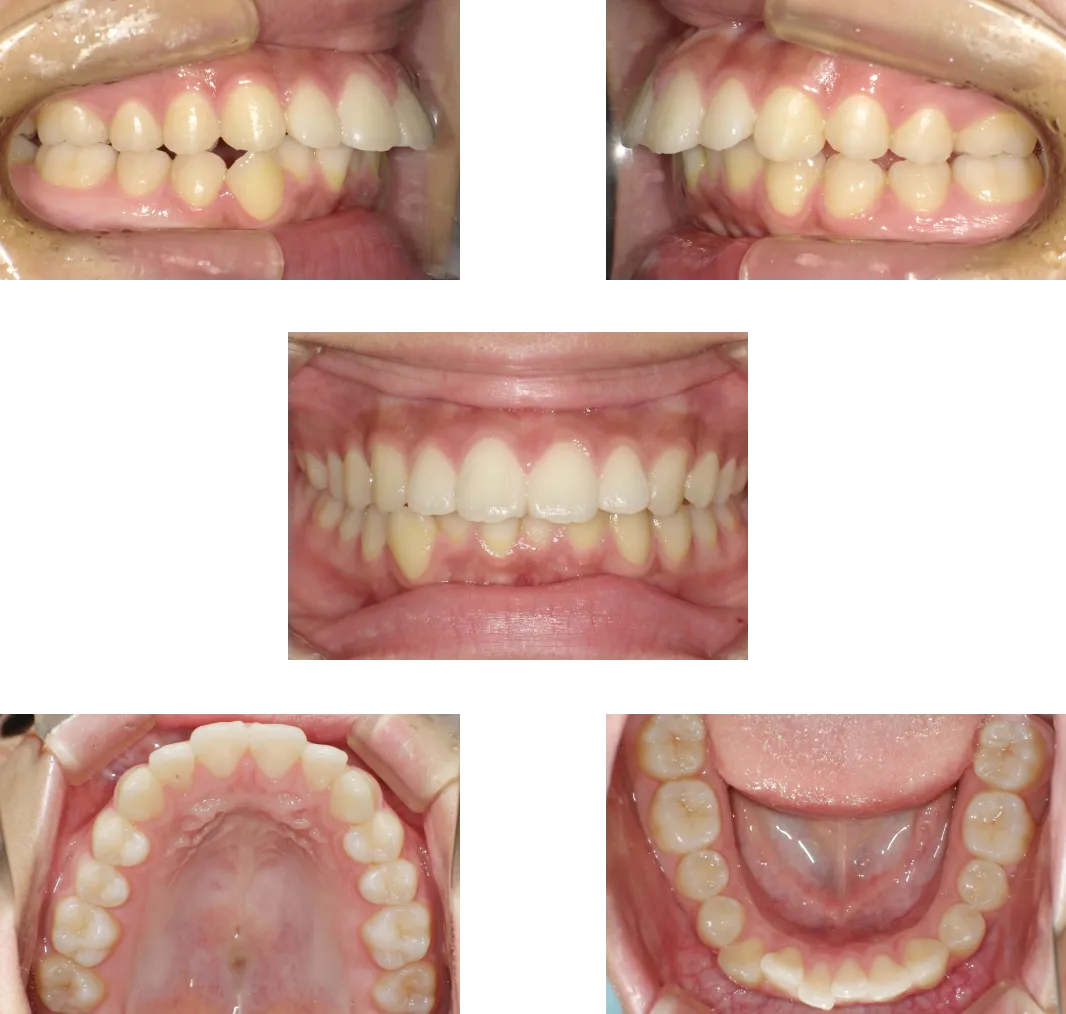

叢生 -39歳-

• Before

• After

診断

両側顎関節の変形

治療期間

1年6ヶ月+保定期間2年

料金

1,060,000円

抜歯

なし

リスク

痛み、軽度の歯根吸収、術後の変化